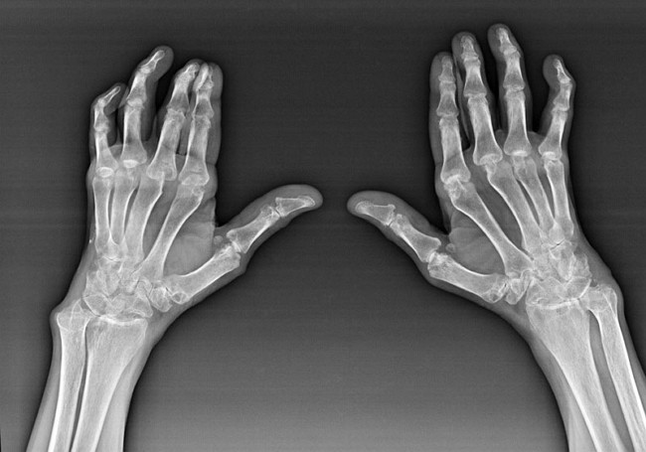

Artrita reumatoidă

Artrita reumatoidă este o boală în care sistemul imunitar uman dăunează propriilor țesuturi ale organismului. Cu alte cuvinte, artrita reumatoidă este o patologie autoimună. Această boală este, de asemenea, sistemică, deoarece multe țesuturi sunt afectate de aceasta (mușchi, articulații, vase etc.) și organe (Inima, rinichii, plămânii etc.) în corp.

În ciuda faptului că artrita reumatoidă este o boală sistemică sub ea, într -o măsură mai mare, articulațiile suferă, în timp ce leziunea altor țesuturi și organe este pe fundal. Cu această boală, aproape toate tipurile de articulații perii pot fi afectate (pereți de mână, căi de carpali, articulații metacarpal-phalanx, interpalanx) Leziunea este de obicei simetrică (aceste. Aceleași articulații sunt afectate) Pe ambele mâini, însoțite de umflare, durere în articulațiile deteriorate. Dimineața, în timpul ridicării din pat, există o oarecare rigiditate în articulațiile afectate, care pot dura aproximativ 1 oră și apoi să dispară fără urmă.

Destul de des cu artrită reumatică în apropierea articulațiilor afectate ale periei (mai des articulațiile de pian-pian-fonic) Apar noduli reumatoizi. Sunt o formațiune rotunjită situată sub piele. Pe perie, aceste formațiuni apar cel mai des pe spate. La palpare, sunt densi, inactivi, nedureroși. Numărul lor poate varia.